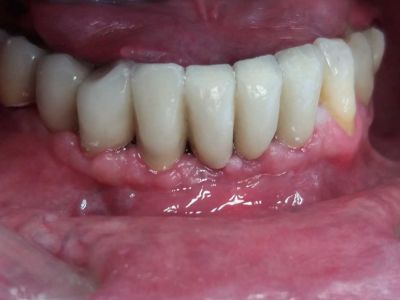

PRIMA

Il paziente è arrivato alla nostra attenzione con problemi gengivali ed elevata mobilità dei denti frontali inferiori, che li rendeva purtroppo non più recuperabili.

Dopo le estrazioni,abbiamo inserito 3 impianti ai lati dei 2 già presenti.